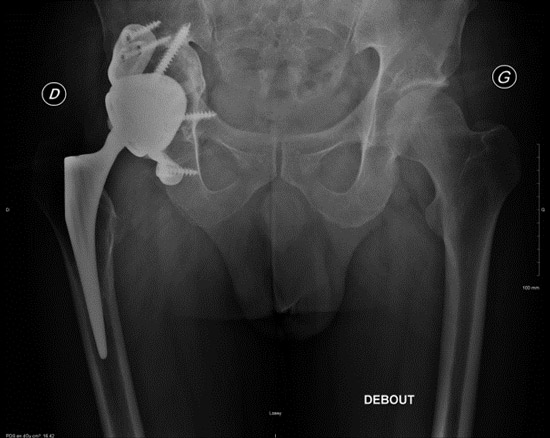

Postoperative imagery